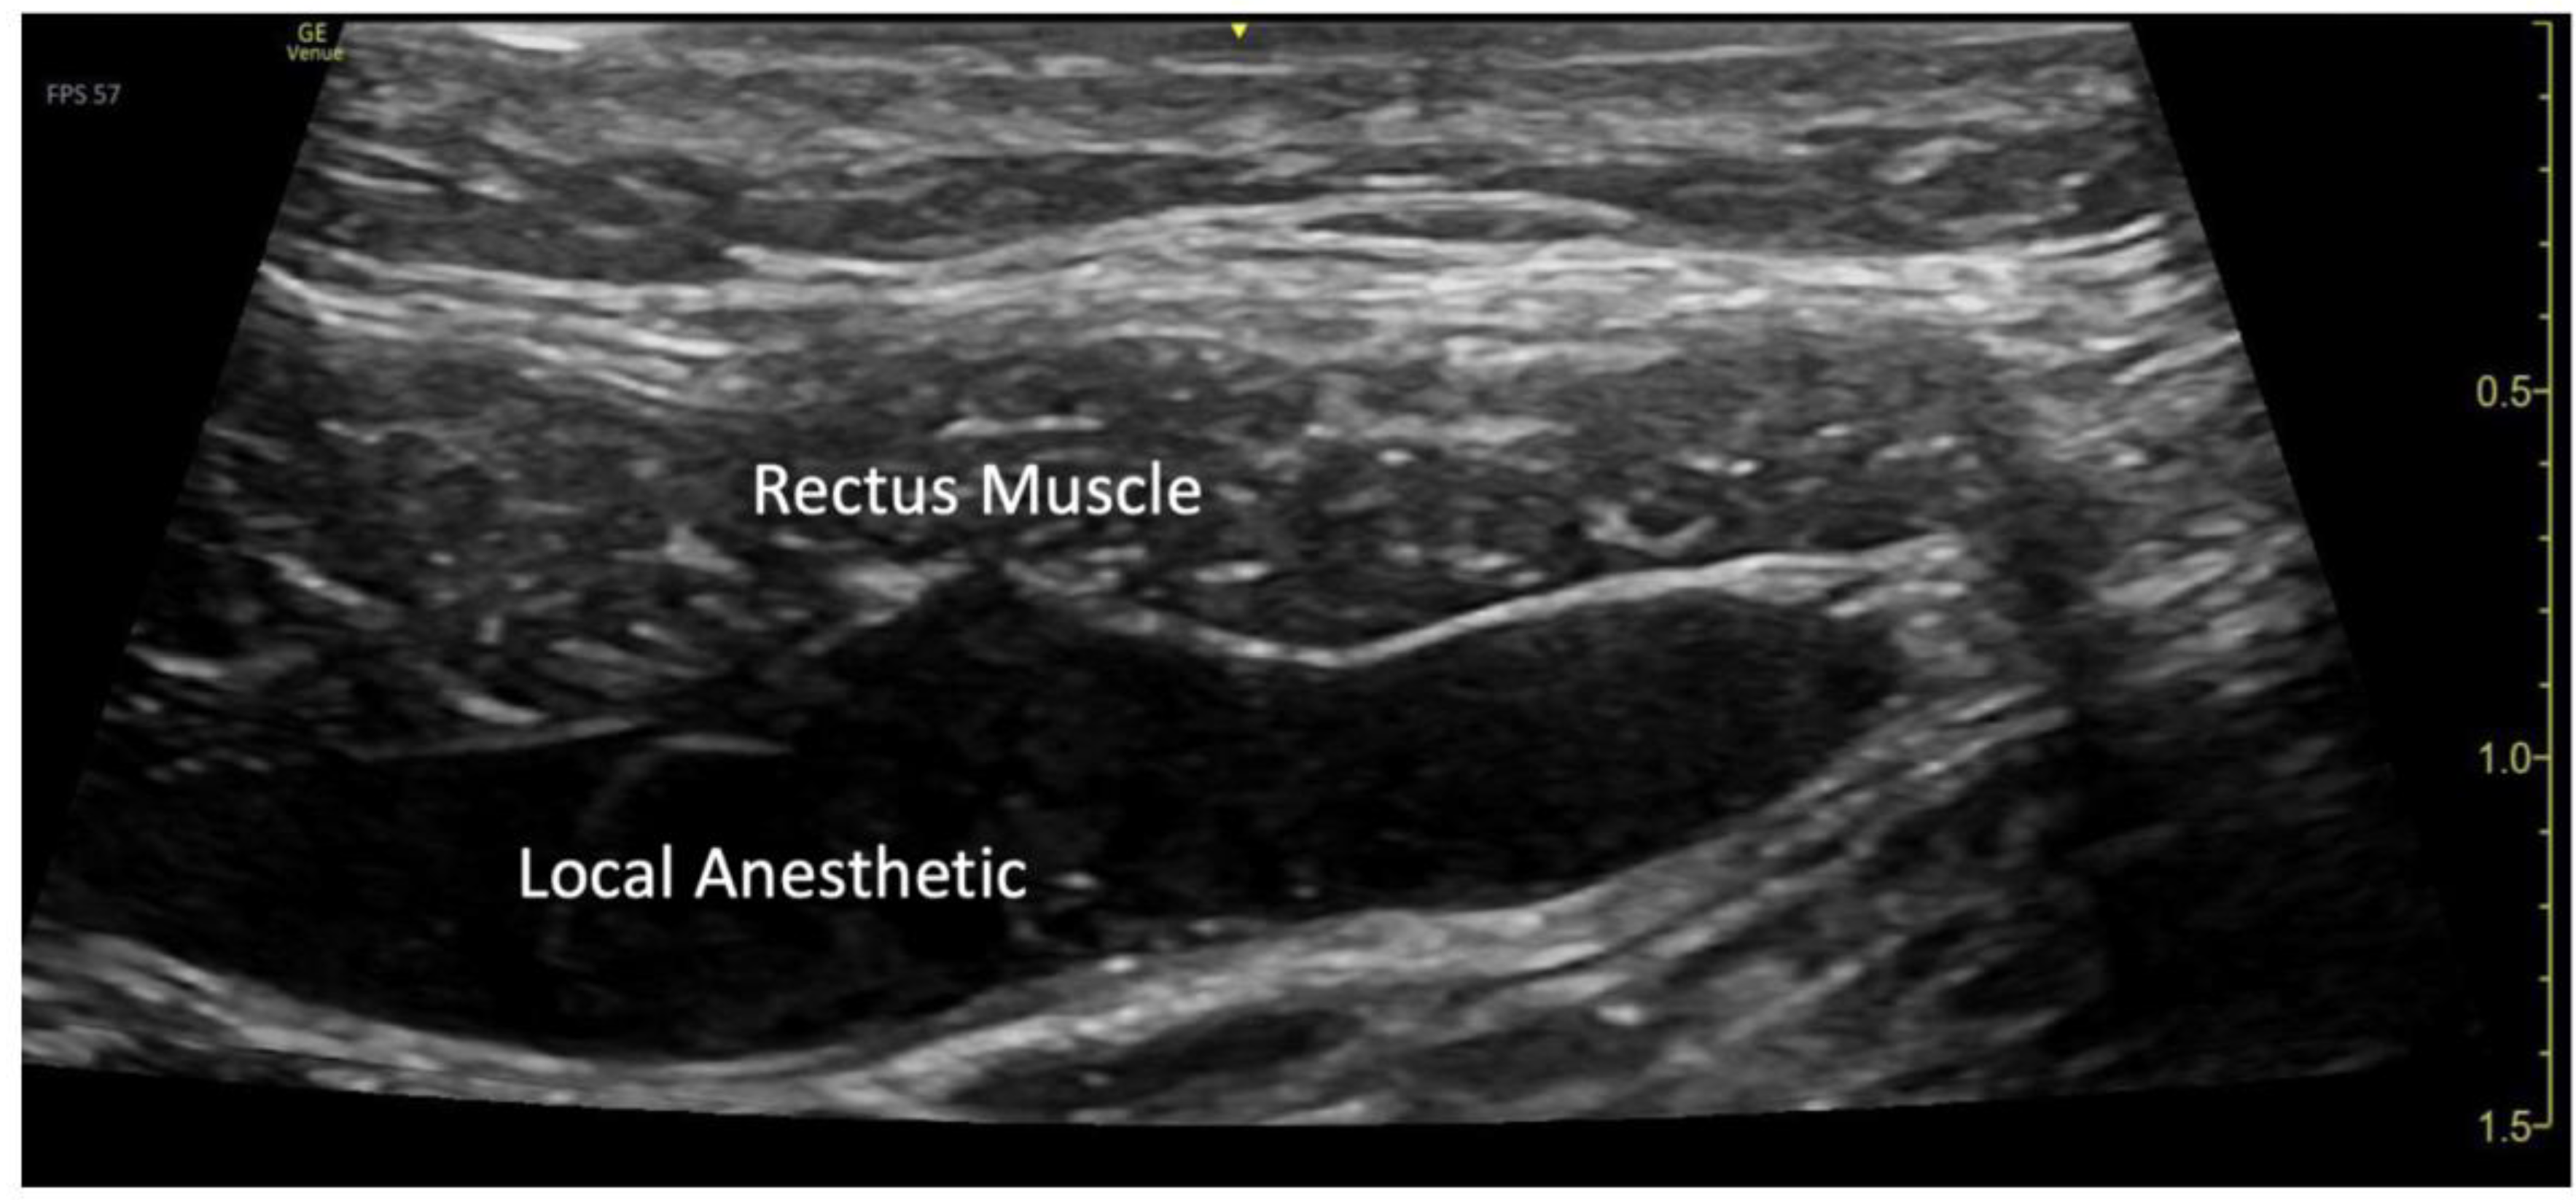

The blocks were performed while the patient was under general anesthesia, before surgery started, and after sterile preparation. A high-frequency linear transducer was positioned at the level of the umbilicus and moved laterally a few centimeters until the lateral border of the rectus muscle was visualized. An echogenic needle, 22-gauge, 50-mm Sono-TAP (Pajunck Medical Inc., Geisingen, Germany) was advanced medially from the lateral edge of the probe; final needle placement was at the lateral border of the rectus muscle, deep to the muscle, yet superficial to the posterior aspect of the rectus sheath, and not pre-peritoneal nor intraabdominal. A few milliliters (mL) of saline solution were injected until the spread of medication was visualized in the correct location (Figure 1), followed by three milliliters (mL) of local anesthetic mixture (liposomal bupivacaine 113.05 mg, bupivacaine 0.25%, 32.5 mg, and dexamethasone PF, 5mg -total volume 22 mL). This procedure was repeated at the contralateral site. Two more bilateral local anesthetic injections under the rectus muscle were performed at the level of T7 and T12 dermatomes (Figure 3a). A total of six rectus sheath blocks were performed with 22 ml of local anesthetic mixture. After the blocks were performed, medication spread behind the rectus muscle was visualized as a bulge into the space under the rectus sheath muscle from the xiphoid to the pubic symphysis (Figure 2), as described by Visoiu et al, [18] matching the incision performed (Figure 3b). The surgery then conducted was an open infrarenal abdominal aortic aneurysm repair with a Hemashift Gold 12mm graft and a 6mm limb used for aortic graft to common iliac aneurysm repair. The duration of anesthesia was 374 minutes, the aortic cross-clamp time was 95 minutes, and total blood loss for the operation was 50mL. The surgery was uneventful, and intraoperative hemodynamic stability was adequately maintained. The patient was extubated in the operating room.

Figure 2. Visualization of local anesthetic spread under the rectus muscle.